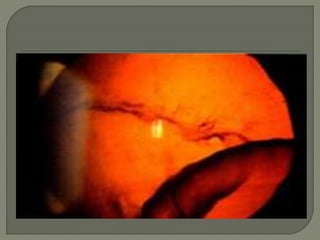

 Slit lamp examination:

- Bread crumb appearance

- Polychromatic luster

- The earliest finding is a polychromatic lustre at the

posterior pole of the lens which may not progress if

the uveitis is arrested. If the inflammation persists,

posterior and anterior opacities develop that may

progress to maturity. The opacities appear to

progress more rapidly in the presence of posterior

synechiae.